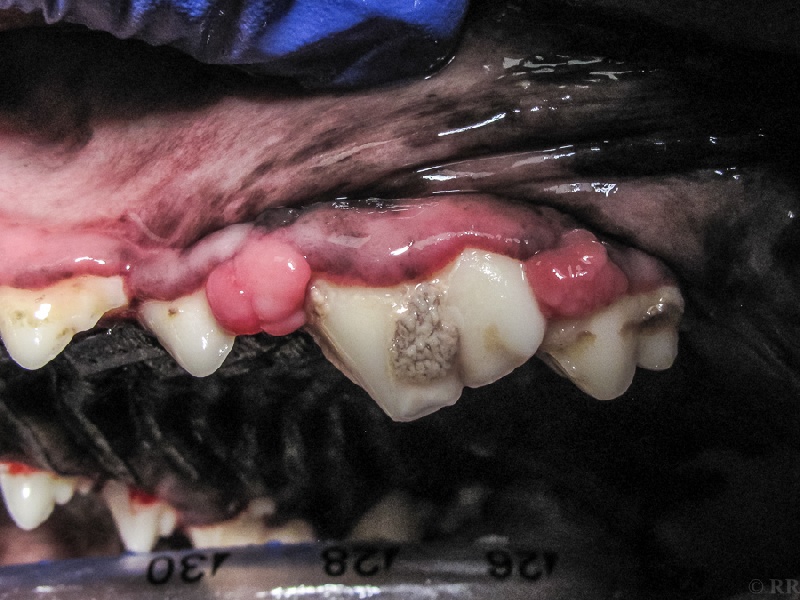

Auf dem Bild sehen wir zwei sogenannte Epuliden (Einzahl: Epulis). Epuliden sind sehr häufige und aus chronischen Entzündungen entstehende Zahnfleischwucherungen, die sich dankenswerterweise nicht wirklich bösartig verhalten und recht einfach entfernt werden können. Manche von ihnen können den Kieferknochen erfassen, was dann eine erfolgreiche Resektion erschwert. Sie bilden aber im Gegensatz zu den echten malignen (bösartigen) Tumoren der Mundhöhle immerhin keine Metastasen (Tochtergeschwülste).

Ob man es aber wirklich nur mit Epuliden - und nicht mit Schlimmerem - zu tun hat, ergibt sich erst aus einer Gewebeprobe. Deshalb sollte auch beim Verdacht "nur" auf Epuliden zügig etwas unternommen werden. Übrigens: Die Hunderasse, die querbeet eine geradezu extreme Neigung zur Bildung von Epuliden zeigt, ist der Deutsche Boxer. Die Besitzer eines Boxers sollten deshalb sehr häufig die Mundhöhle ihres Hundes kontrollieren.